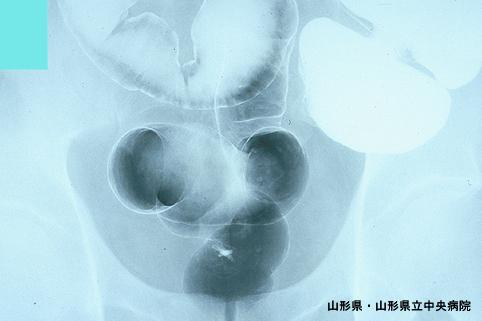

A case of multiple small carcinoma tumors of the rectum with lymphnode metastasis.

Yamagata Pref., Yamagata Prefectural Central Hospital (Dr.池田)

Carcinoid tumor/

Large intestine(Colon)/Rectum

X-ray

1 - 9

submucosa

Synchronous